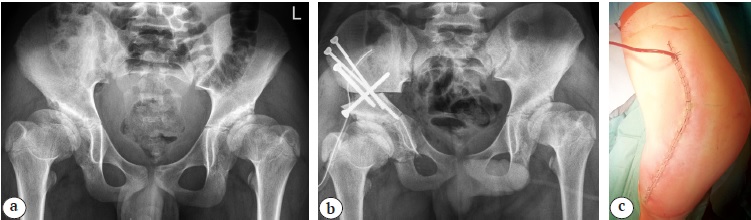

Переднебоковой доступ. Положение пациента на операционном столе — лежа на контралатеральном пораженному суставу боку. Выполняется углообразный разрез кожи и подкожно-жировой клетчатки от передне-верхней ости подвздошной кости до уровня границы верхней третей диафиза бедра длиной 15–20 см. Рассечение tensor fascia lata повторяет разрез кожи с дополнительным поперечным сечением кзади на уровне большого вертела с целью проведения манипуляций на седалищной кости. После препаровки промежутка между m. gluteus medius и m. tensor facia lata и выделения крыла подвздошной кости осуществляется рассечение хрящевого апофиза гребня подвздошной кости с последующим поднадкостничным выделением тела подвздошной кости, в которую проводится проволочная пила. Следующим этапом выполняются поднадкостничное выделение и остеотомия лонной кости медиальнее Y-образного хряща или гребневидного бугорка максимально близко к вертлужной впадине. После выделения на протяжении n. ischiadicus выполняются поднадкостничное выделение и периацетабулярная остеотомия седалищной кости краниальнее места прикрепления lig. sacrotuberosus. После этого проводится остеотомия тела подвздошной кости с последующей реориентацией либерализованной вертлужной впадины (рис. 1).

Рис. 1. Выполнение тройной остеотомии таза из переднебокового хирургического доступа: a — рентгенограмма пациента 12 лет с дисплазией тазобедренных суставов I степени по Crowe до операции; b — рентгенограмма после восстановления корректных соотношений между тазовым и бедренным компонентами тазобедренного сустава методом реориентирующей тройной остеотомии таза справа; c — фото хирургического доступа после ушивания